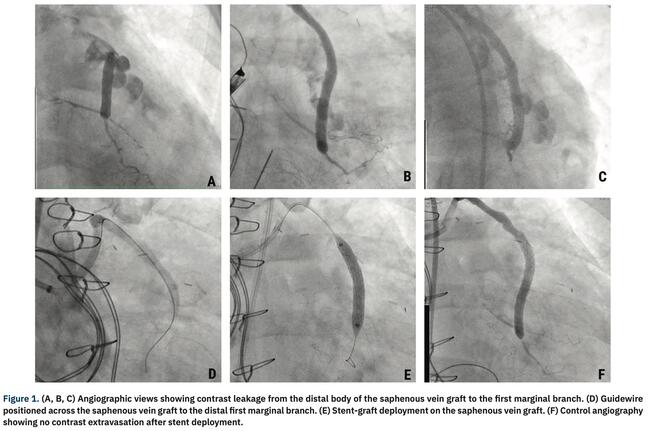

Clinical Images

Emergency Percutaneous Treatment of Saphenous Vein Graft Perforation After Cardiac Surgery

A 58-year-old woman presented to the emergency department with a non-ST segment elevation myocardial infarction. She was referred for coronary artery bypass graft surgery due to severe multivessel coronary artery disease.

In the immediate postoperative period, the patient had excessive bleeding through the chest drains and hemodynamic instability, followed by total atrioventricular block requiring use of temporary pacemaker, which precluded electrocardiographic interpretation. During the next hour, bleeding reduced but the patient remained hemodynamically unstable and was referred for urgent diagnostic coronary angiography.